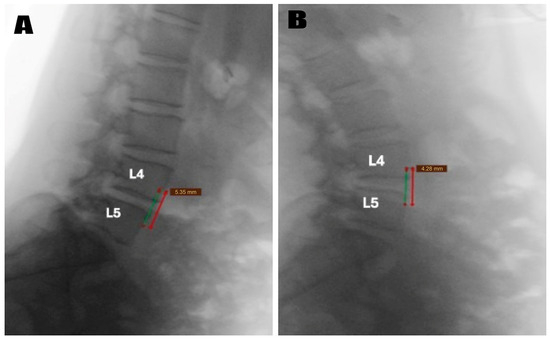

Preoperative MRI confirmed the diagnosis radiologically (Figure 1). Dynamic flexion-extension radiographs were obtained in all patients preoperatively (Figure 2) to evaluate segmental instability and to minimize selection bias that may occur due to the retrospective nature of the study. Cyst excision alone was performed in patients without instability according to imaging results, and unilateral dynamic instrumentation was performed (Figure 3) in addition to excision in patients with grade 1 instability according to the Meyerding classification. The systematic protocol used for decision-making reduced the impact of personal choices on selection of treatment. Patients with spondylolisthesis above grade 1 were not involved in the study. Exclusion of these patients provided sample homogeneity in addition to the biomechanic success of PEEK rod systems in mildly unstable cases due to their flexible designs.

Figure 2. Preoperative dynamic lateral radiographs of the same patient, demonstrating segmental instability at the L4–L5 level. (A) A flexion radiograph showing 5.35 mm anterior translation of L4 over L5 as measured from the vertebral body reference lines (red and green lines). (B) An extension radiograph showing 4.28 mm anterior displacement of L4 over L5 as measured from the vertebral body reference lines. The measurements demonstrate Grade 1 spondylolisthesis according to Meyerding classification. Both images confirm segmental instability that warrants unilateral dynamic stabilization in addition to cyst excision.